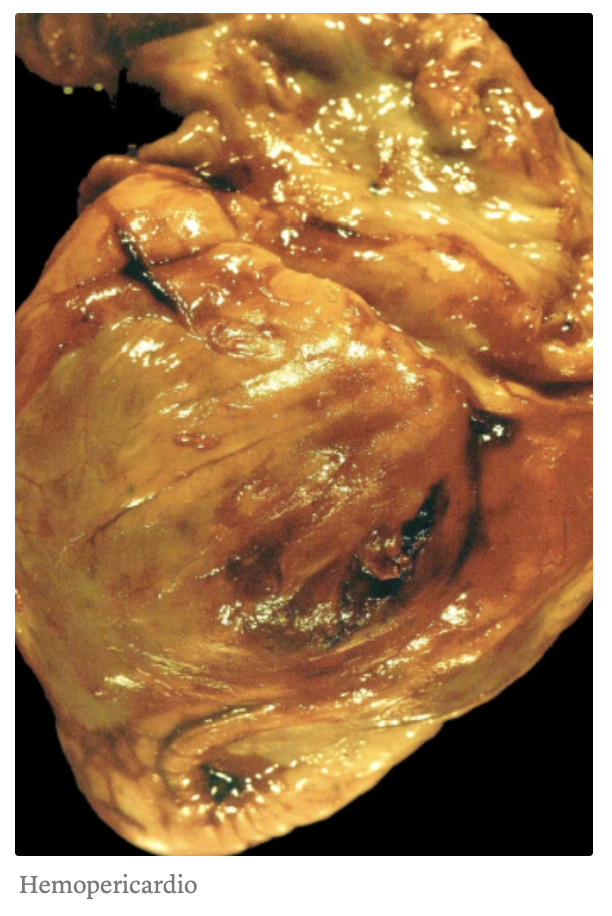

Hemopericardio: acumulación de sangre, principalmente por rotura cardiaca